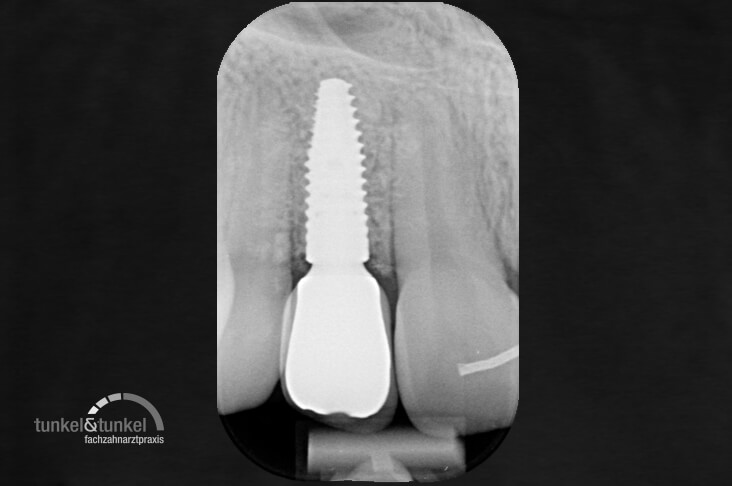

Mit dem Einpflanzen künstlicher Zahnwurzeln sind wir in der Lage, verlorene Zähne komplett zu ersetzen. Mit den so genannten Implantaten stellen wir einen funktionellen und ästhetischen Zahnersatz her, der die Nachbarzähne nicht schädigt und auch herausnehmbare Prothesen ersetzt. Durch unsere modernen Methoden und Techniken können wir zudem den Aufbau des zahntragenden Knochens unterstützen, so dass praktisch bei jedem Patienten Implantate eingesetzt werden können.

Seit mehreren Jahrzehnten gibt es jetzt schon Implantate, die es ermöglichen einen verlorenen Zahn durch einen wirklich Neuen zu ersetzen. Hierbei handelt es sich um künstliche Zahnwurzeln aus Titan, die vom Körper als nicht-fremd akzeptiert werden und mit dem eigenen Knochen verwachsen. Die Unterschiede zwischen echten Zähnen und den künstlichen Implantaten werden vom Patienten nicht wahrgenommen.